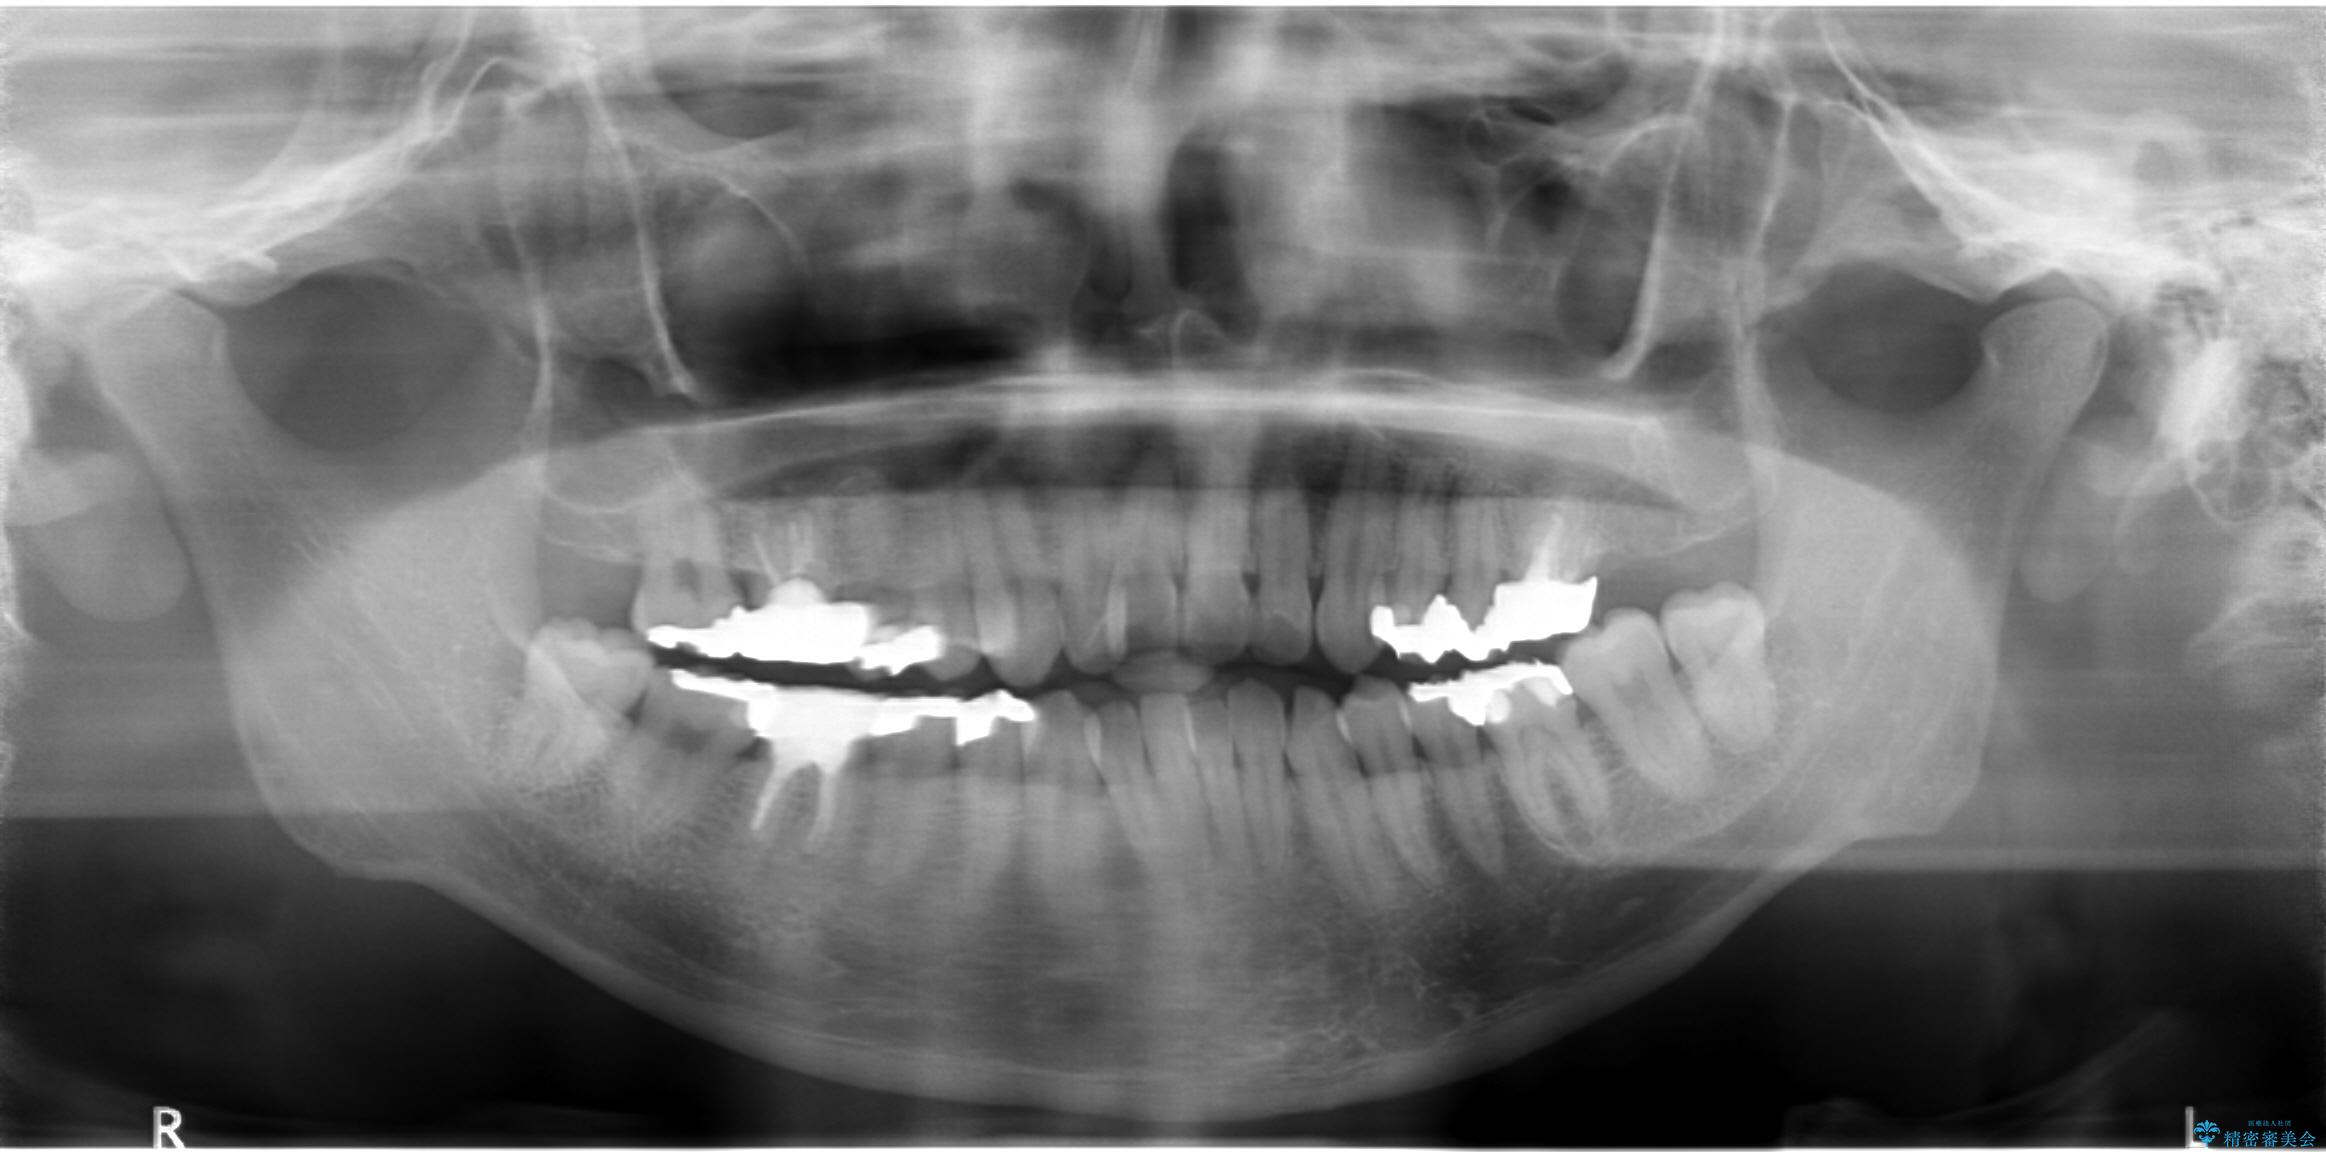

- 突き出た前歯の角度の改善と虫歯治療の改善を求めて来院されました。

虫歯を除去したのち、マウスピース矯正治療を行い、歯並びやがたつきを改善したのち、セラミックに置き換えることで審美性の向上を計画します。